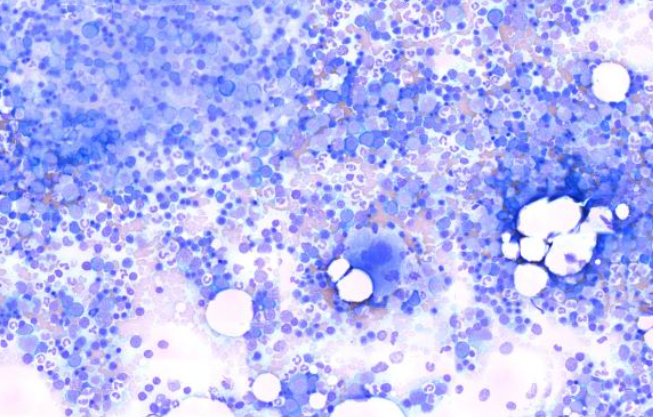

Normal bone marrow 11521041658_5152

골수 / 정상 / 개

Normal canine Sample: bone marrow aspiration(골수흡인표본)